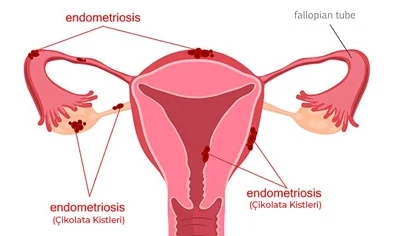

Kisti olup hamile kalanlar kist hamile kalmaya engelmidir kist varken hamile kalınırmı kist hamile kalmamda sorun yaratırmı kist ve gebelik hakkında bilgiler bazı kadınlar kistleri oldugu için bazen hamile kalmayabilir ancak 3 cm lik kisti olupta hamile kalan birsürü insan var. şubatta kontrole gideceğim umarım ben de hamile kalabilirim hayırlısıyla. Adet sancıları şiddetli olan derin cinsel ilişkide ağrısı olan karında ve kasıkta ağrıları bulunan kanlı dışkılama idrarda yanma ve kanama olması adet kanaması olduğunda burun kanaması olan vücudunda değişik yerlerde morluklar oluşan ve üreme çağında olan kadınların çikolata kisti açısından tehdit altında. çikolata kisti hamile kalmayı nasıl engeller.

Kisti olup hamile kalanlar. çikolata kisti olup sol tüpü kapalı hamile kalanlar çikolata kisti. Bunun opere olması şart değil. şubatta kontrolüm var dua ediyorum o zamana kadar hamile kalayım diye teşekkür ederim geçmiş olsun size de dermoid kistler ilaçla küçülmüyor maalesef benim de ilk dr görmemişti kisti alttan ultrasonla bakmasına rağmen 2.

Kizlar ankarada 2 devlet kadindogum hastanesi gezdim ama beni mahvettiler. çikolata kisti olup sol tüpü kapalı hamile kalanlar çikolata kisti. Merhaba kistler türüne göre gebe kalmada sıkıntı yaratır çikolata kisti de hamile kalmaya engel olan kistler den biri. Kistimin polikist oldugunu adet gorunce gectigini soylediler ve suan 2 yillik evliyim ozel hastane adini cok duydugum hulisi bulent zeynelogluna gittim dermoid kistimin oldugunu soyledi ameliyat oldum bugun 3.